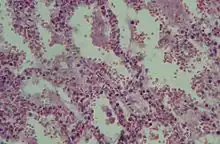

Histologie

Le SDRA est causé par une altération de la membrane alvéolocapillaire entraînant un syndrome lésionnel appelé « dommage alvéolaire diffus » entraînant une dysfonction sévère de l'oxygénation du sang et une hypoxémie sévère.

Le dommage alvéolaire diffus (DAD) comporte 3 stades[12] :

- Phase aigüe, exsudative : dépôt de membranes de fibrine le long des parois alvéolaires :

- infiltrat diffus neutrophilique avec hémorragie, destruction des pneumocytes I,

- œdème riche en protéines, fibrine + surfactant inactivé comblant les alvéoles pulmonaires,

- altération des pneumocytes II, diminution de la synthèse du surfactant pulmonaire,

- dure à peu près 6 jours ;

- Phase subaigüe, proliférative :

- hyperplasie, métaplasie des pneumocytes II,

- début d'organisation fibreuse,

- dure de 4 à 10 jours ;

- Phase chronique :

- réorganisation fibreuse interstitielle.